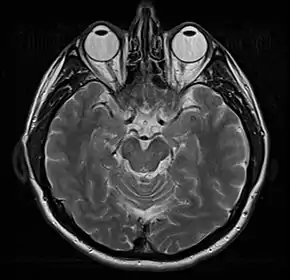

This axial T2-weighted (CSF white) MR scan shows a normal brain at the level of the lateral ventricles.

• T2-weighted (T2W) images: CSF is light, but fat (and thus white matter) is darker than with T1. T2-weighted images are useful for visualizing pathology.[25]